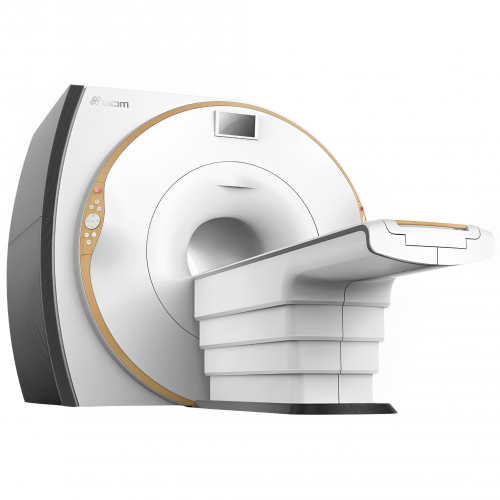

CR Wandong recently released its i_Magnate 1.5T optical superconducting MRI system. This system uses the most advanced optical technologies for transmitting radio frequency signals and parallel image processing technology over 8-32 channels. This ensures excellent image quality and high scanning speed.

The new i_Magnate 1.5T has a large Open Bore design and a very short system. This can give you a feeling of comfort when scanning. Thanks to the new mobile device management technology and digital image processing platform, you can enjoy a wonderful experience of intelligent and efficient work.